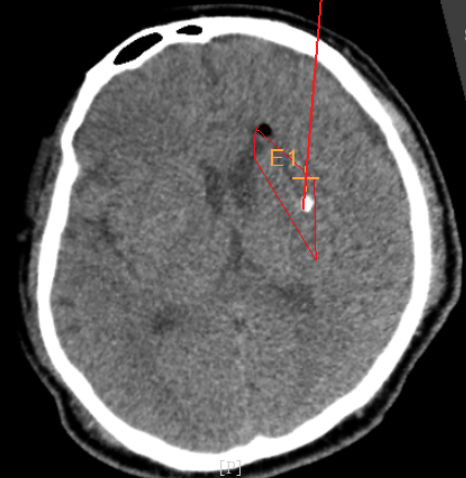

3個月前CT:腦出血

alt text

術前CT:血腫已經(jīng)液化,但仍有占位效應